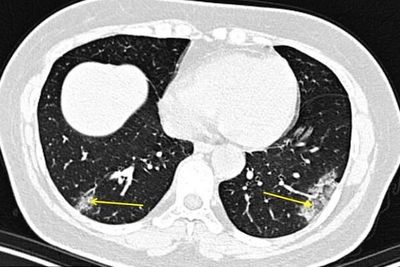

تشخیص سریع ابتلا به کرونا با سی تی اسکن

پزشکان در نیویورک برای نخستین بار در آمریکا اسکن ریه بیماران مبتلا به ویروس کرونا را در چین بررسی کردند. آنها معتقدند با کمک سی تی اسکن می توان الگوهای خاصی را در ریه به عنوان نشانگر ابتلا به ویروس کووید۱۹ شناسایی کرد.

رادیولوژیست ها اسکن های این افراد را بررسی کردند و بر اساس زمان بروز علائم و زمان انجام سی تی اسکن ، نت برداری کردند این روش نشان داد به وسیله سی تی اسکن سریع تر می توان تخریب بافت ریه را ردیابی کرد.